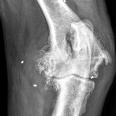

Die Orthopädie beschäftigt sich mit der Entstehung, Verhütung und Behandlung von angeborenen oder erworbenen Problemen des Bewegungsapparates. Die meist daraus resultierenden Lahmheiten werden bei uns umfassend abgeklärt. Hierbei kommen neben einer ausführlichen klinischen Lahmheitsuntersuchung auch weiterführende diagnostische Verfahren, wie Röntgen Computertomografie und Ultraschall zum Einsatz.